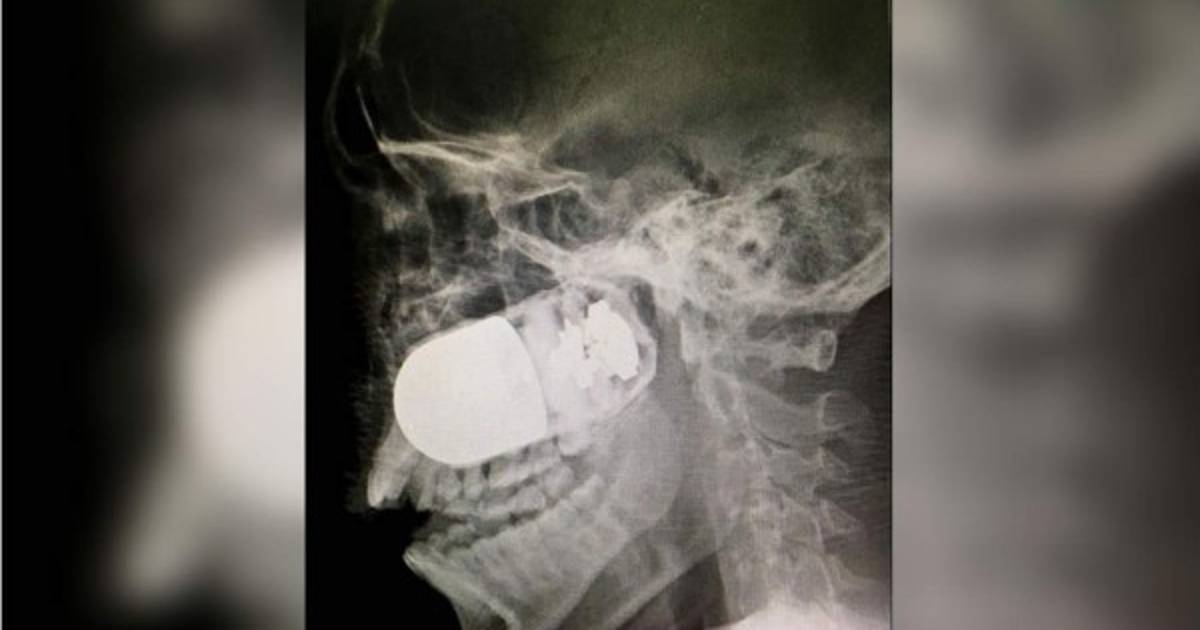

Médicos colombianos extrajeron del rostro de un soldado una granada incrustada durante un accidente con un lanzagranadas, un arriesgado procedimiento que debió realizarse en el aparcamiento del Hospital Militar de Bogotá ante el temor de que el explosivo estallase en quirófano.

La grabación de la delicada intervención, difundida hoy en redes sociales, muestra cómo el equipo quirúrgico retira del pómulo derecho del uniformado un cilindro de unos cinco centímetros de longitud.

La granada se alojó en el rostro del soldado profesional Leandro José Luna el pasado domingo en el departamento de Arauca, fronterizo con Venezuela, cuando los militares patrullaban en una zona cercana al río Tame, detallaron medios locales.

En la capital colombiana fue operado con éxito el domingo en el parqueadero del Hospital Militar, donde se decidieron a operarle por temor a que el explosivo estallara en el quirófano.